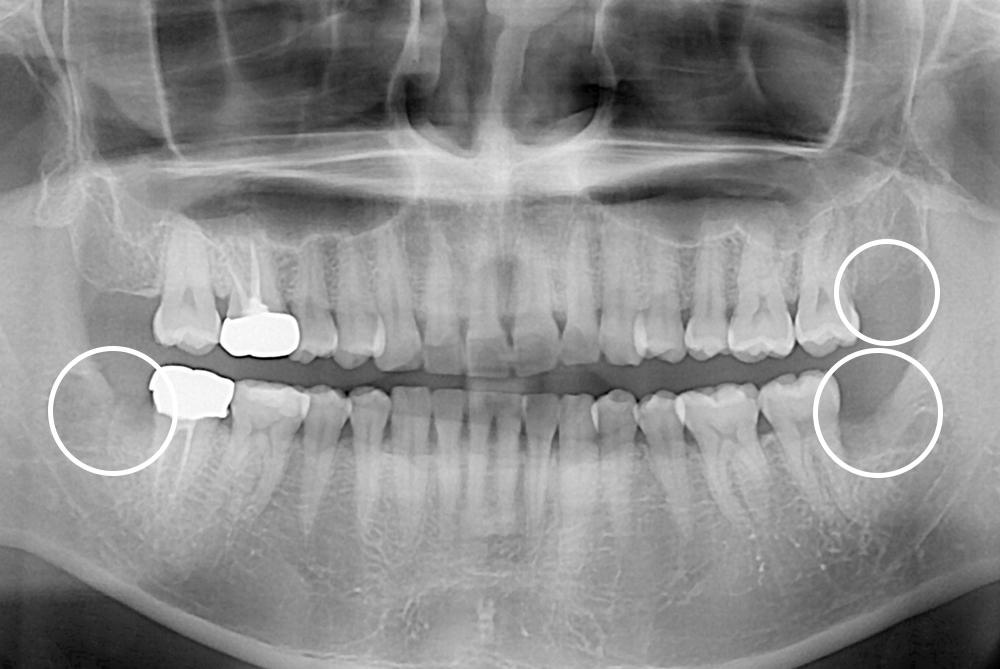

[사랑니] 매복 사랑니 발치

치료후 : 2021-12-01

세종치과는 구강악안면외과학 박사이신 원장님이 발치하는 치과입니다.